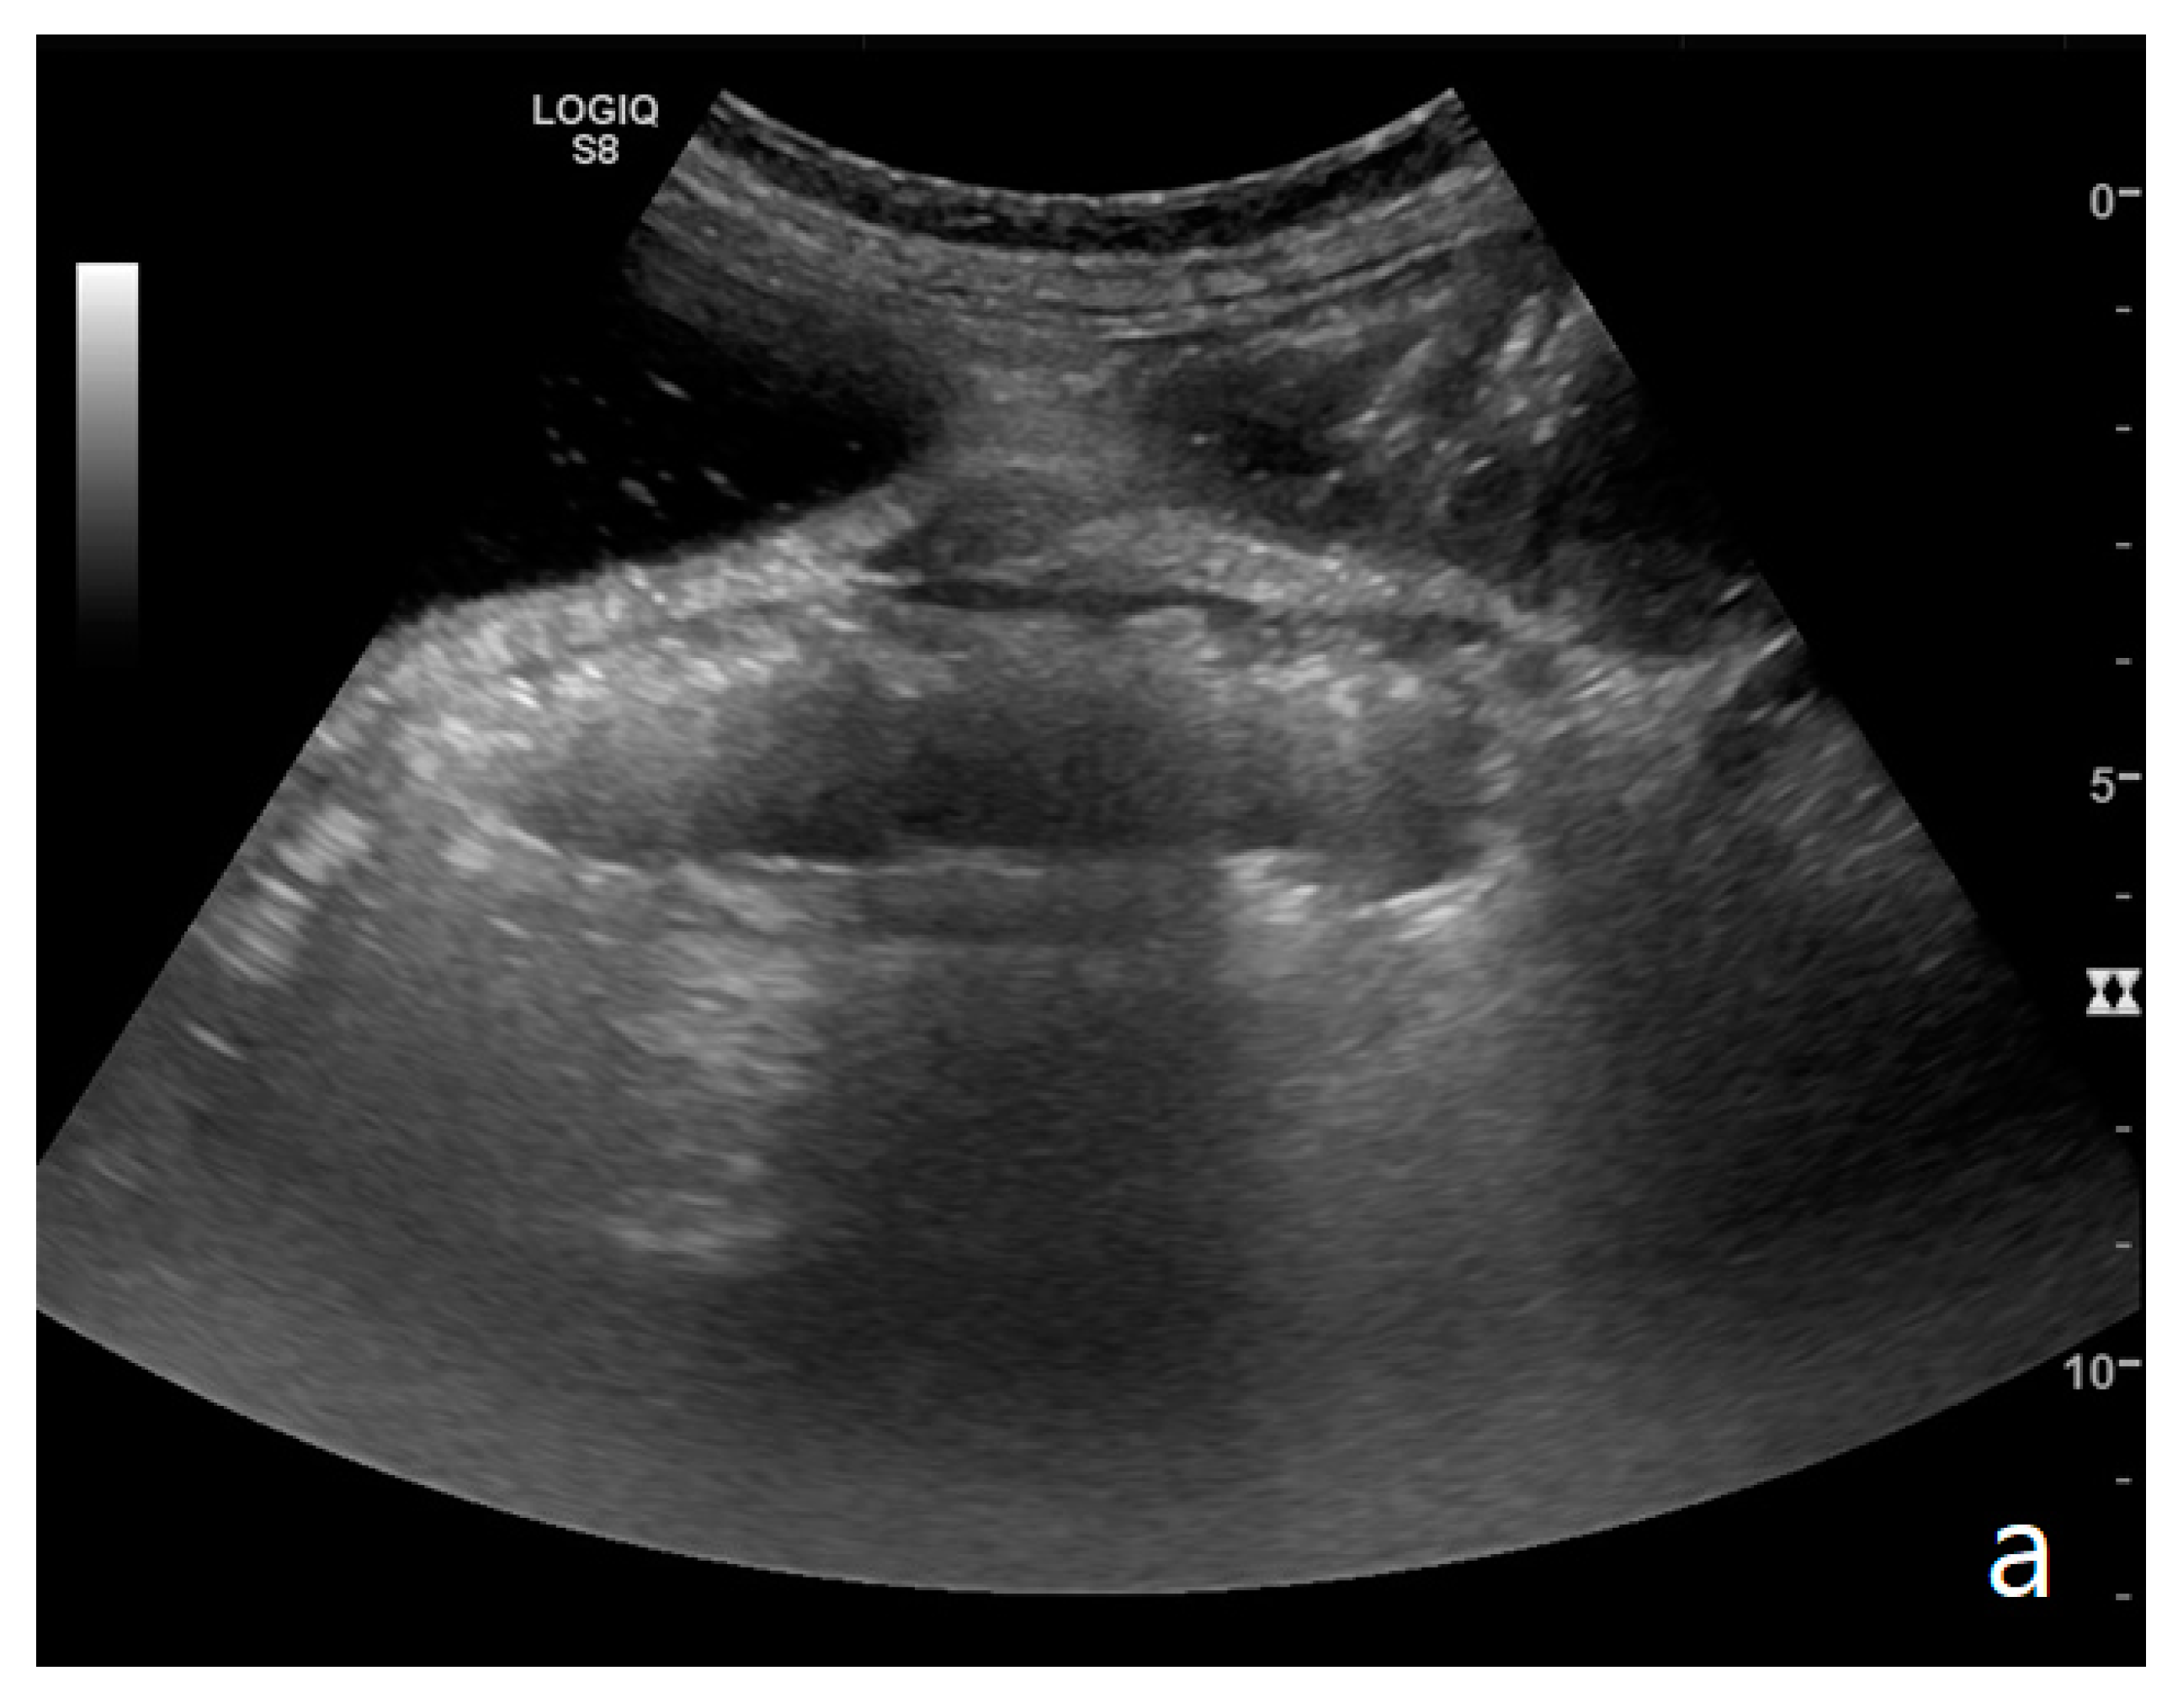

Figure 1.

(a,b). A simple SBO. Ultrasound images show fluid-filled, dilated small bowel loops (a,b) with hyper-kinesis and hyper-representation of valvulae conniventes (white arrow) (a); tail comet artifacts are visible due to air-fluid levels (dashed arrow) (b) and groups of bowel loops with severe differences in diameter (‘bowel jump diameter’) are evident more superficially (*) (b). No free fluid was detected in the abdominal cavity or between bowel loops.